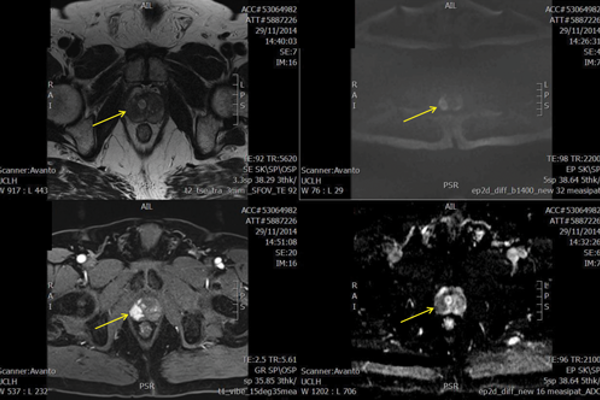

The PROMIS trial – time for multi-parametric MRI before a first prostate biopsy